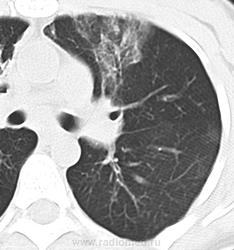

Бронхиальная астма, после курения крэк-кокаина.

Имеются сообщения о поражении других органов и систем, в частности мозга и печени. При внутривенном употребления кокаина нередки инфекционные и эмболические осложнения. При курении сам наркотик или его примеси могут повреждать альвеолярный аппарат легких [8]. При вдыхании кокаина через нос может произойти перфорация носовой перегородки.